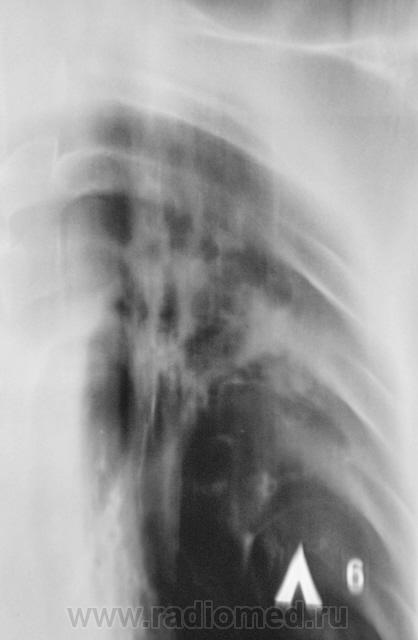

Томограмма - второй срез.